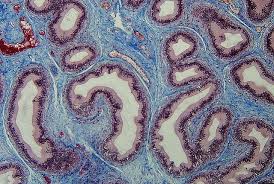

قیمت: 49٬000 تومان - دسته بندی فایل: تحقیقپاورپوینت نارسایی مزمن کلیه (ppt) 27 اسلاید

فروش ویژه پاورپوینت حرفه ای نارسایی مزمن کلیه / تعداد اسلاید: 27 اسلاید

قیمت: 25٬000 تومان - دسته بندی فایل: تحقیقپاورپوینت بافت همبند (ppt) 12 اسلاید

فروش ویژه پاورپوینت حرفه ای بافت همبند / تعداد اسلاید: 12 اسلاید